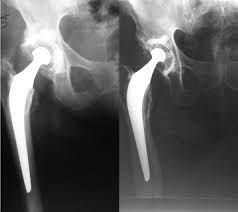

La prothèse totale de hanche est une intervention chirurgicale qui a pour but de remplacer les surfaces articulaires de la hanche (cavité cotyloïdienne les alternatives à cette intervention vous ont bien été expliquées. La majorité des gens sont très satisfaits de cette intervention. Il convient de r�p�ter les essais de laboratoire et les essais.

La prothèse de hanche remplace l'articulation défaillante par deux composants solidement fixés à l'os, mais mobiles l'un par rapport à l'autre.